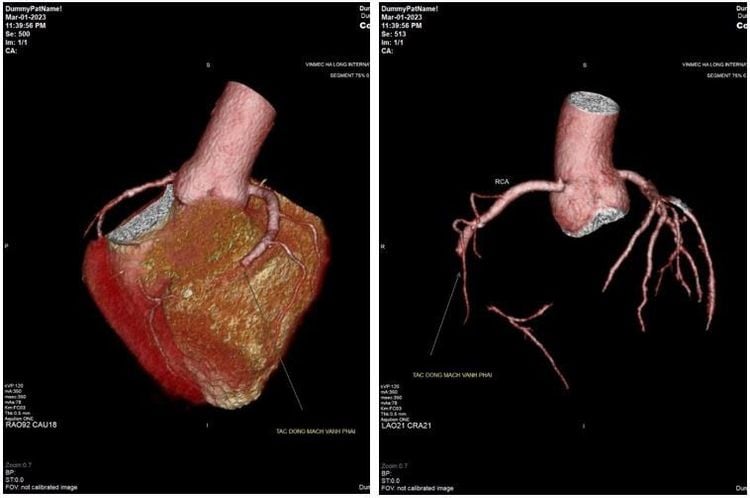

Chẩn đoán phân biệt nhồi máu cơ tim

Một bệnh nhân 32 tuổi người Trung Quốc đã được đưa từ Móng Cái đến Bệnh viện ĐKQT Vinmec Hải Phòng do có cơn đau thắt ngực trái, khó thở. Với tiền sử hút thuốc lá nhiều năm, rối loạn Lipid máu không điều trị. Khi bệnh nhân nhập viện, với bệnh cảnh thăm khám, bác sĩ đã nghĩ đến tình trạng nhồi máu cơ tim động mạch vành. Tuy nhiên, trên siêu âm tim không thấy rõ rối loạn vận động vùng trên siêu âm tim, nghĩa là xét nghiệm không tương xứng với hình ảnh lâm sàng, bệnh nhân cần tầm soát bệnh lý động mạch chủ thêm để phân biệt với các bệnh lý động mạch chủ, bệnh lý động mạch vành. Kết quả là chụp MSCT động mạch chủ và động mạch vành cho thấy người bệnh có tình trạng tắc hoàn toàn động mạch vành phải từ đầu đoạn RCA3.

Với kết luận bệnh nhân bị hội chứng động mạch vành cấp, các bác sĩ đã có đủ cơ sở để đưa ra chỉ định can thiệp ngay và không cần trì hoãn nữa. Trong quá trình chụp động mạch vành qua da (DSA) để can thiệp đặt Stent cũng cho thấy kết quả tương xứng: Tắc hoàn toàn đoạn 3 của động mạch vành phải. Sau khi được can thiệp tái thông bằng 2 Stent, 3 ngày sau, bệnh nhân đã không còn các cơn đau ngực, vận động đi lại bình thường. Kết quả theo dõi nhiều tháng liền sau đó bệnh nhân dung nạp tốt, không có biểu hiện suy tim cho thấy các chẩn đoán và can thiệp là hoàn toàn chính xác và tối ưu.

Chia sẻ về ý nghĩa khi chụp MSCT trong trường hợp này, BS Quý cho biết thêm: “Nhồi máu cơ tim là bệnh nguy hiểm có thể đe dọa tử vong. Ở người trẻ tuổi như bệnh nhân này, nguyên nhân nhồi máu cơ tim thường do tổn thương nội mạch động mạch vành, gây tình trạng huyết khối cấp tính (hay gặp ở người bệnh hút thuốc lá, có các yếu tố nguy cơ như béo phì, rối loạn lipid máu, tăng huyết áp, đái tháo đường). Hiện tượng calci hóa trong động mạch vành (vôi hóa mạch vành) là một dấu hiệu sớm của bệnh mạch vành. Vôi hóa mạch vành lâu ngày tạo thành các mảng xơ vữa tích tụ trong thành động mạch vành, dẫn đến hẹp lòng động mạch vành và làm giảm lưu lượng máu đến nuôi tim gây ra những cơn đau ngực hay nhồi máu cơ tim. Với các trường hợp nhồi máu cơ tim còn nghi ngờ như trường hợp bệnh nhân này, cần loạn trừ hội chứng động mạch chủ cấp thì MSCT có vai trò quan trọng và có định hướng trong can thiệp động mạch vành”.